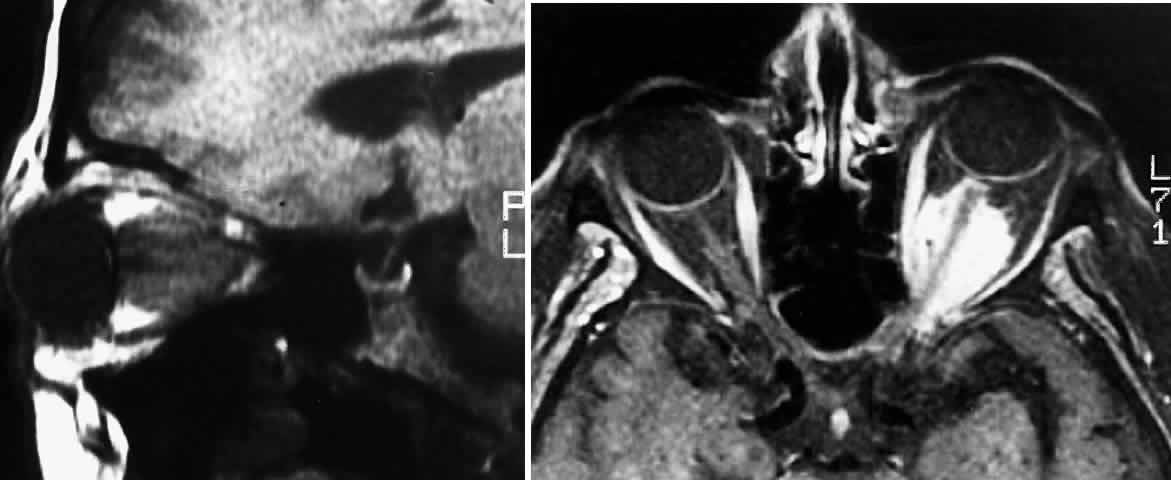

| Plain-film orbital X-ray may reveal concentric enlargement of the optic

foramen with preservation of a well-corticated margin due to a slow growth

of the tumor.4 A criterion for abnormality in one study that did not include any false-positives

in children is an optic foramen of 7 mm diameter, or 6.5 mm

and at least 1 mm larger than the contralateral foramen.67 Enlargement of the optic canal does not necessarily imply intracranial

extension of the glioma, because dural thickening and arachnoid hyperplasia

may cause such changes.68,69 In the series of Chutorian and colleagues, foramen enlargement was present

in 83% of patients with involvement of one optic nerve and in 67% of

those with chiasmal involvement.29 The pressure of the glioma on the anterior clinoid process and lateral

chiasmatic groove may produce a fossa with continuity of the optic canal, creating

a J-, pear-, or gourd-shaped sella turcica.70 Tumors that less commonly produce a similar flattening include trans-canalicular

extension of intraorbital neurofibromas, perioptic extension

of a craniopharyngioma, or pituitary adenoma.4 With the availability of computerized tomography (CT) and magnetic resonance imaging (MRI), invasive diagnostic techniques such as arteriography and pneumoencephalography should not be performed in the routine workup of presumed optic gliomas.71 CT scanning may demonstrate enlargement of the optic nerve or chiasm by a glioma (Fig. 3). Because optic gliomas typically appear isodense to normal brain,72 and because the degree of contrast enhancement ranges from imperceptible to moderate on CT imaging,73 the margins of the tumor may not be well delineated. Optic gliomas usually have a well-outlined fusiform shape, which may include kinking or buckling of the optic nerve. Chiasmal tumor appearance may range from a tubular thickening of both optic nerves and chiasm to massive, multilobular growths.74 Cystic spaces representing mucinous accumulation have been described. These cysts may enlarge and damage adjacent structures, requiring surgical intervention.74,75 Calcific change has also been documented in gliomas, but it is a rare radiologic finding.13 In following patients clinically, it is important to understand that radiologic progression of optic gliomas on CT scans may not correlate clinically with worsening visual function. Conversely, a decline or improvement in visual status may occur despite a lack of corresponding changes on neuroimaging.73,76 MRI has replaced CT scanning as the optimum test for imaging optic gliomas (Fig. 4 A and B). Optic gliomas have normal to slightly prolonged T1 relaxation times and appear isointense to slightly hypointense to normal brain on T1. Because many of these tumors have prolonged T2 relaxation times, images that are T2 weighted may be used to assess gross tumor margins and posterior extension.72 Optic nerve gliomas often demonstrate minimal enhancement after administration of contrast. To improve MR imaging of optic nerve lesions, a gadopentetate dimeglumine enhancement technique combined with fat suppression can be utilized. Unlike meningiomas, the thickened sheath from arachnoid hyperplasia associated with gliomas will not enhance.77 Although imaging should initially be performed in the axial plane to allow visualization of both the optic nerve and the posterior optic pathways, sagittal views are helpful in demonstrating chiasmal involvement; coronal views can be utilized to delineate intracanalicular tumor.78 MRI has several advantages over CT scanning. In addition to sparing children from exposure to ionizing radiation when multiple scans are required, MRI eliminates bony artifact and is superior in evaluating the intracanalicular, chiasmal, and postchiasmal extension of the tumor.78 Brown and associates79 reported 10 posteriorly located lesions by MRI, none of which were visualized by CT. Anterior pathway lesions were detected with equal sensitivity by both modalities. Unfortunately, microscopic spread of gliomas can go undetected by both CT and MRI. In addition to detecting bilateral optic nerve glioma, other MRI findings can suggest an association between an optic nerve glioma and NF-1. One imaging characteristic to watch for is double-intensity tubular thickening, which is seen as a high T2 signal surrounding the optic nerve. This radiologic finding has been termed a “pseudo-CSF” signal and can be misinterpreted as cerebrospinal fluid in a dilated subarachnoid space.80 The high T2 signal arises from perineural arachnoidal gliomatosis, a histopathologic pattern most commonly seen in NF-1-associated gliomas.60 Elongation of the nerve secondary to axial growth of the perineural tumor as well as downward kinking of the nerve in the midorbit are other features suggestive of NF-1-related gliomas.80 Neuroimaging studies have demonstrated that NF-1 patients may have more extensive glioma involvement of the visual pathway than patients who do not have NF-1.79,81 Despite this difference in visual pathway involvement, the same investigators81 noted a lower incidence of progressive neurologic deficits and visual symptoms in NF-1-related glioma patients compared with patients whose gliomas were unrelated to NF-1. MRI scanning of NF-1 patients may also demonstrate aqueductal stenosis, idiopathic macrocephaly, and unidentified T2-weighted signals in the basal ganglia, internal capsule, midbrain, cerebellum, and subcortical white matter.51,64,82 In the appropriate clinical setting, characteristic neuroimaging appearances consistent with intrinsic optic pathway enlargement can usually permit a diagnosis without a surgical biopsy.13,71 Hoyt and associates73,74 noted the following radiologic features on CT scanning that they considered diagnostic for optic chiasm gliomas:

Globular tumors in the suprasellar area that lack these features usually require craniotomy and biopsy confirmation. Lesions that may be difficult to distinguish from optic pathway gliomas include germinomas of the visual system and optic nerve choristoma because they both may appear intrinsic to the visual pathway.13 Tumors such as craniopharyngiomas and pituitary adenomas usually do not appear intrinsic to the visual pathway and may have features of sellar enlargement. Findings such as enhancement of the leptomeninges or peripheral enhancement of an enlarged chiasm are atypical of optic glioma and may indicate an inflammatory process masquerading as a glioma.83 Aneurysms in the suprasellar area may sometimes appear on neuroimaging to be intrinsic to the visual pathway. Better definition may be noted with magnetic resonance angiography.13 In contrast to orbital optic nerve gliomas, meningiomas enhance strongly with gadolinium and are less common in children. Meningiomas have the following features on axial CT scanning that are not typically shared by optic nerve gliomas: